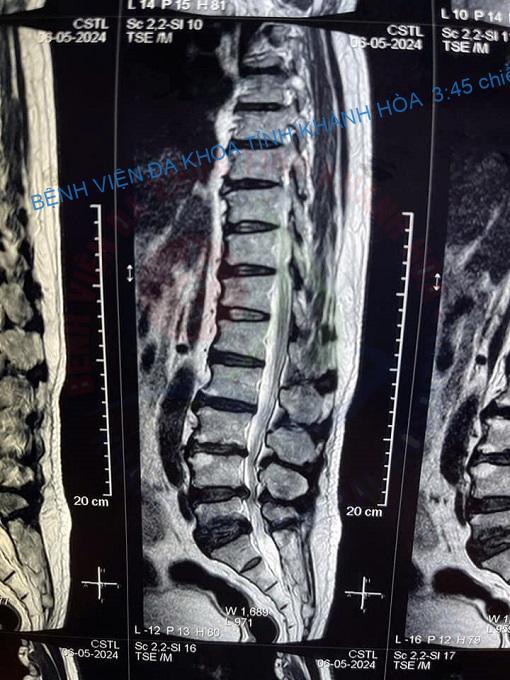

Sau một thời gian điều trị thoát vị đĩa đệm cột sống thắt lưng tại khoa VLTL-PHCN, Bệnh viện Đa khoa tỉnh Khánh Hòa, chú N.T.T. (56 tuổi) chia sẻ: “Chú điều trị ở đây gần được một tháng rồi, cảm giác giảm đau lưng, giảm tê bì rõ rệt sau mỗi buổi điều trị. Phòng điều trị rộng rãi, sạch sẽ, mát mẻ, bác sĩ và kỹ thuật viên tận tình là điều chú rất thích. Mỗi buổi điều trị đều rất thoải mái, thư giãn, có hiệu quả nên chú rất hài lòng”.